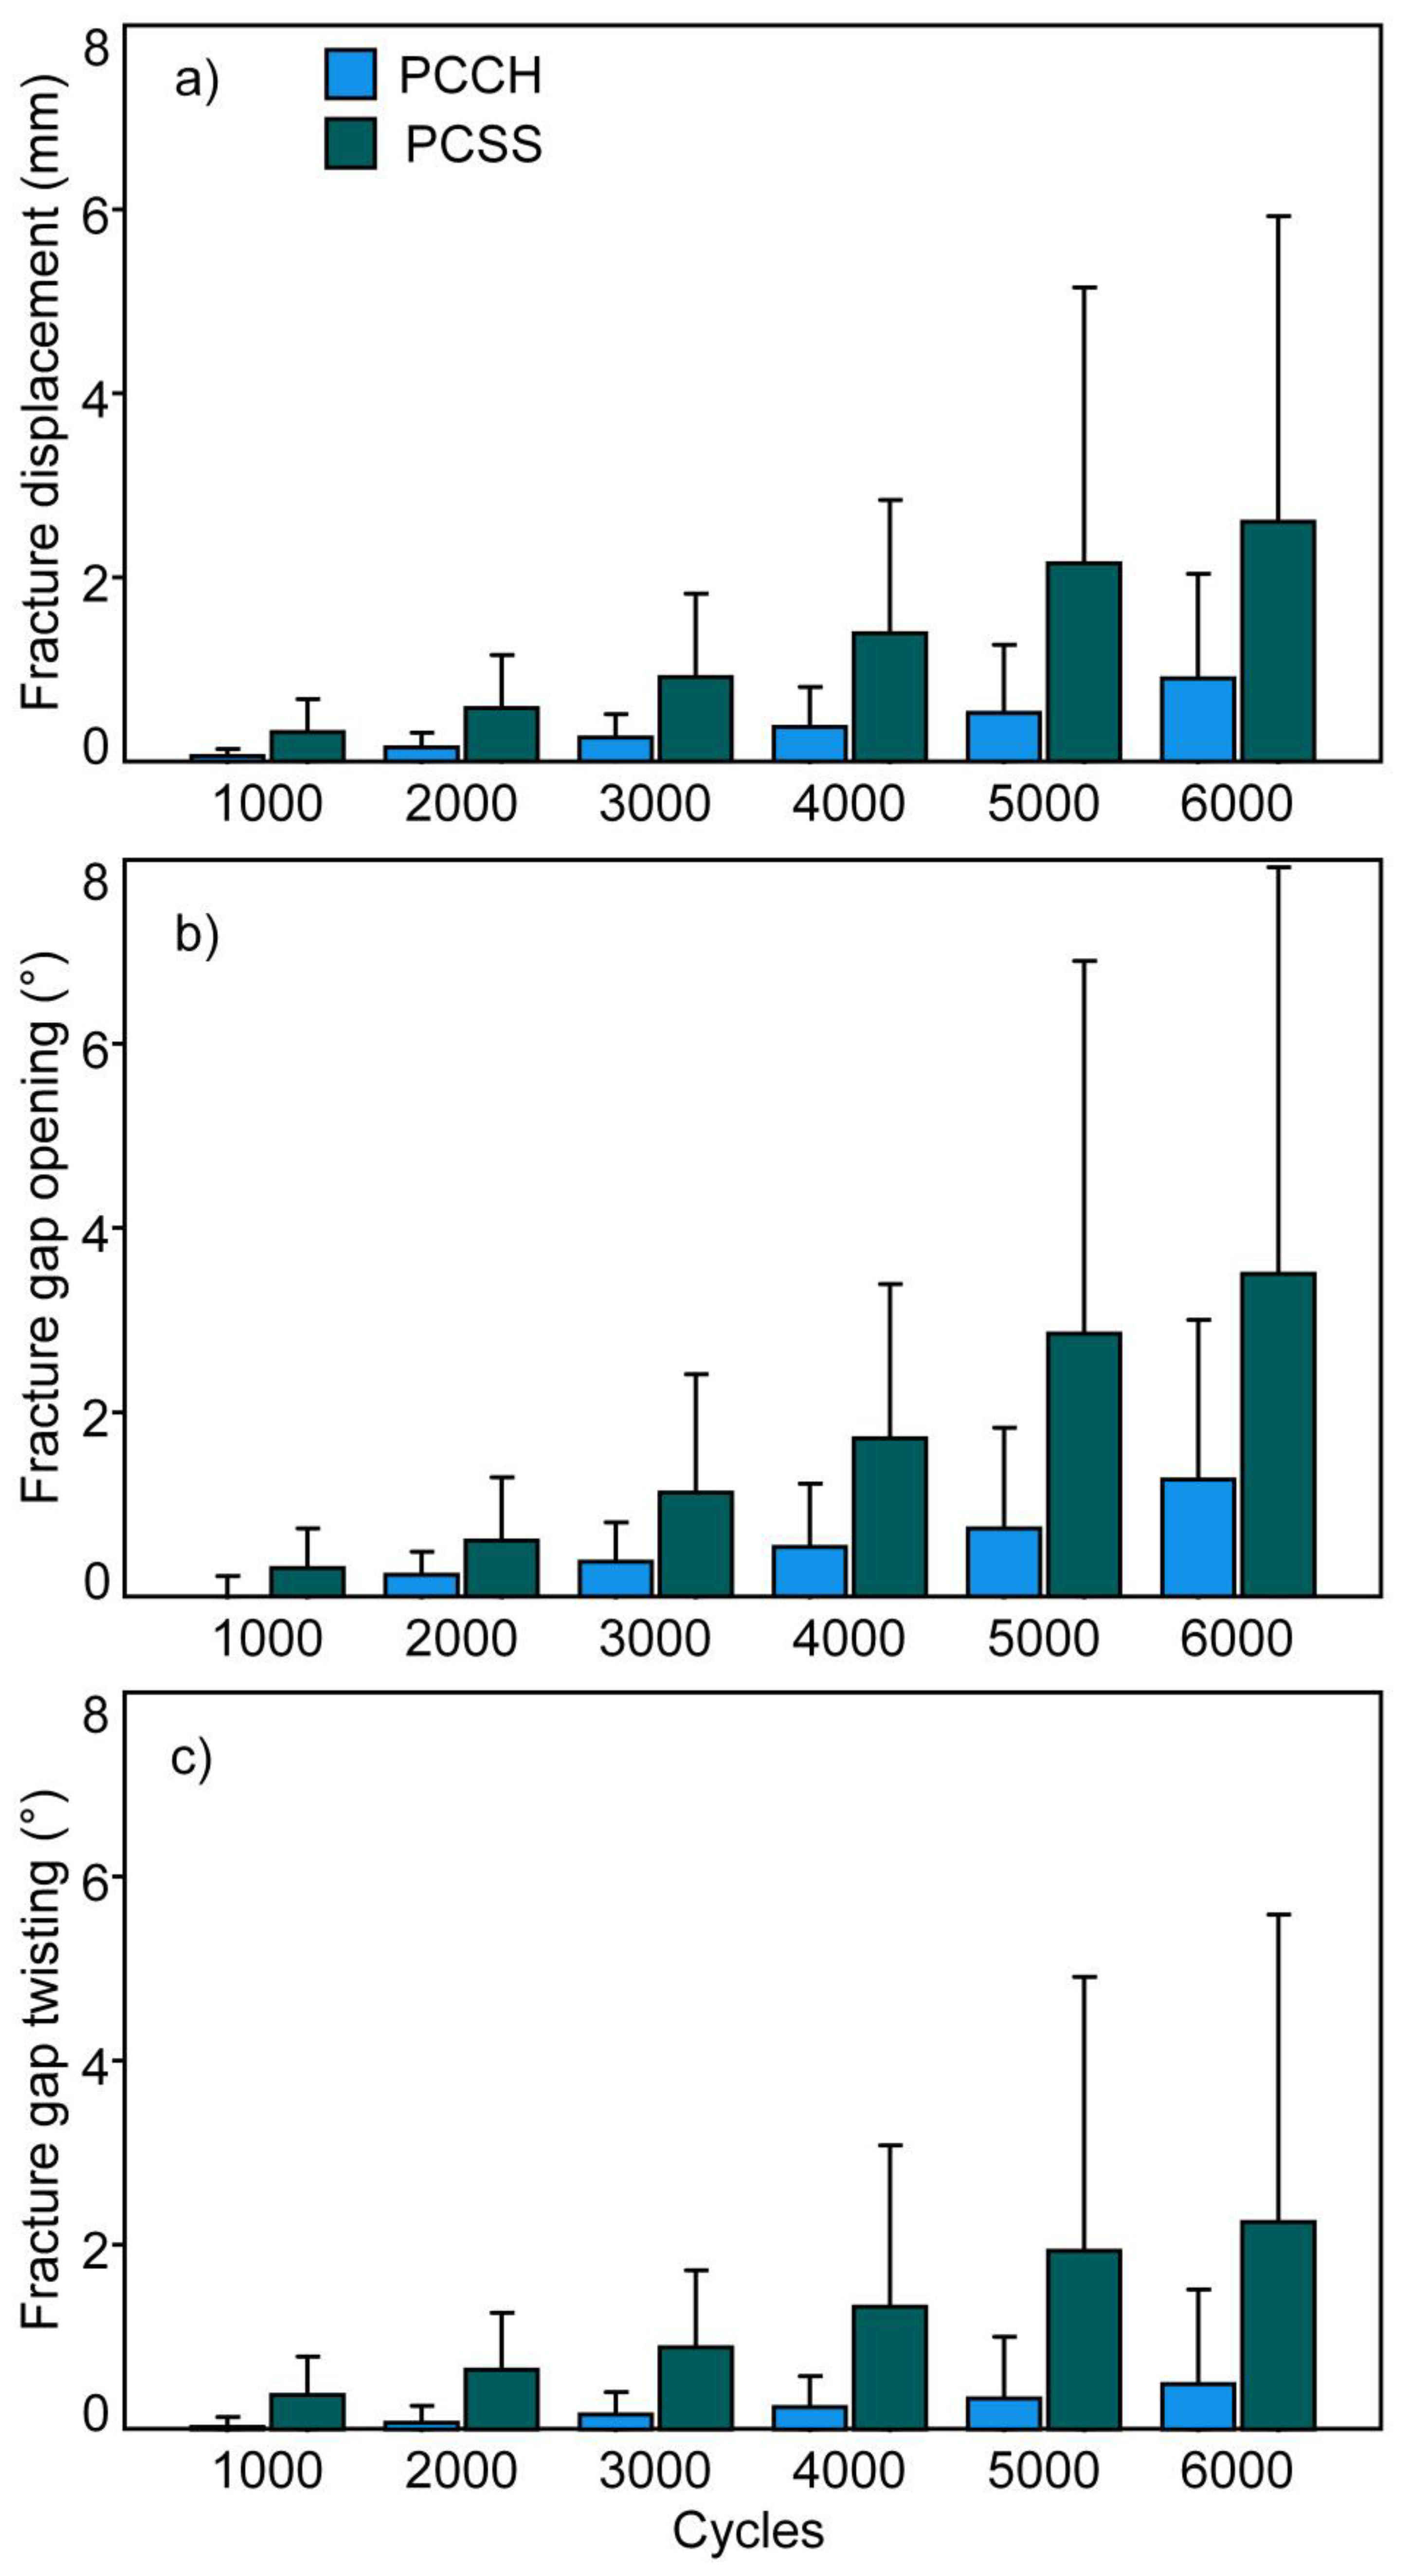

3. Results

- PCCH was associated with significantly higher construct stiffness versus PCSS.

- PCCH demonstrated significantly fewer interfragmentary movements during the first 6000 test cycles compared to PCSS.